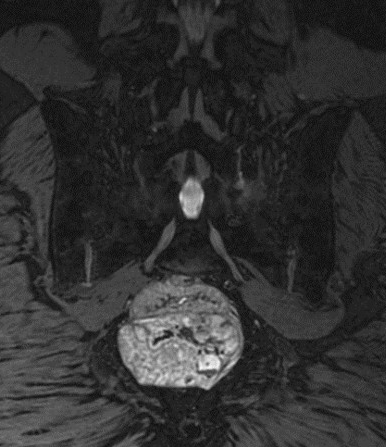

入院后,脊柱与骨肿瘤病区王栋主任牵头,赵波副主任医师、郭帅主治医师团队仔细检查,全面评估。超声穿刺活检提示脊索瘤(经典型),影像检查提示肿瘤位于第3、4骶椎,大小约6.2cm×6.7cm×6.4cm,突入盆腔压迫直肠,近端第2骶椎部分骨质已破坏,侵犯双侧骶2及以远神经根。

赵波副主任医师介绍,脊索瘤是一种罕见的缓慢生长的恶性骨肿瘤,通常发生在脊柱或颅底,其中骶尾部约占40%-50%,颅底脊索瘤约占1/3。脊索瘤起源于胚胎时期的脊索残留物,如果在神经轴的任何部位存在脊索组织残余,即可发展为脊索瘤。又因为骶骨前方骨盆内容积较大,很多患者在疾病发展的早中期,甚至没有一点不舒服的感觉,直到出现大便不畅、小便异常、会阴部疼痛(神经损伤)等各种症状后,才会进一步检查。很多脊索瘤难以完全清除,极易残留,因此容易复发,属于局部侵袭性强的罕见恶性肿瘤。